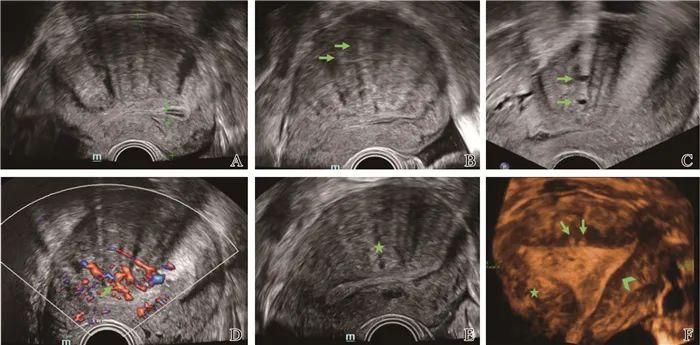

在妇科领域,刘富发运用肘搓八髎术,10秒30次高频共振,可穿透至盆腔纾解粘连。

一名子宫腺肌症患者经十几次的调理后,病痛消失。

这一案例不仅让患者重获健康,更让肘滚技法在妇科领域也大放异彩。